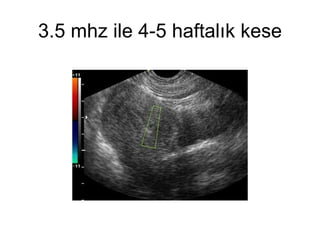

3.5 mhz ile 4-5 haftalık kese

3.5 mhz ile4-5 haftalık kese